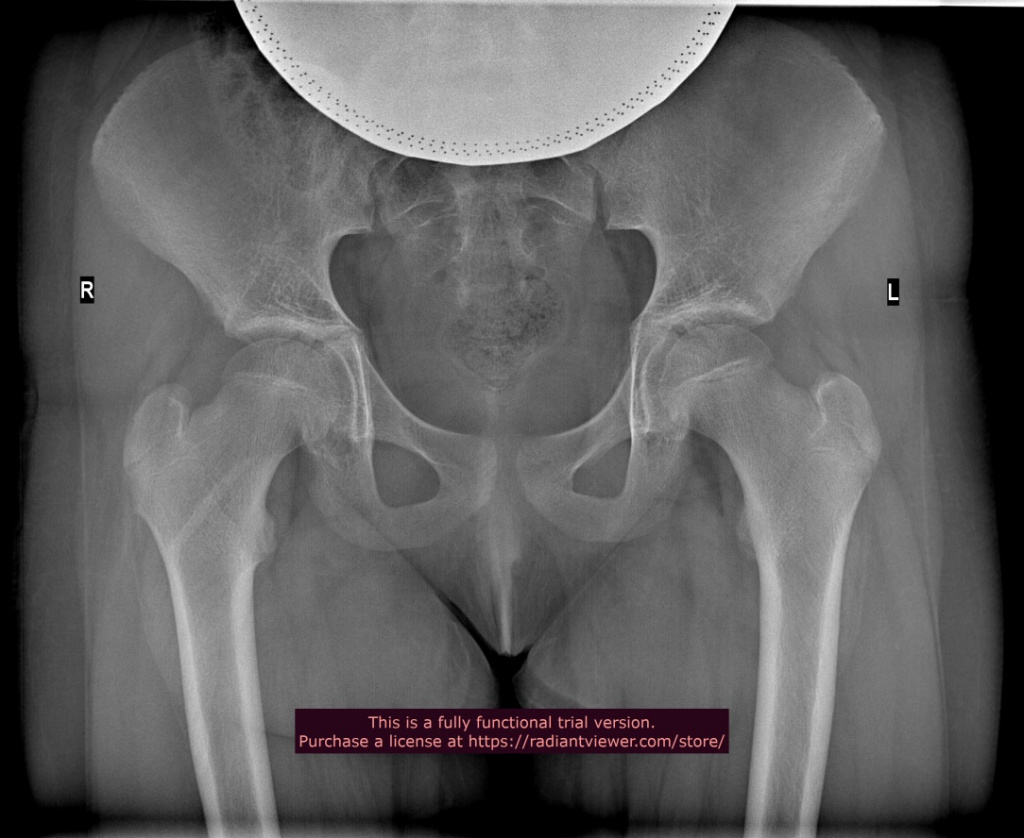

2019 год Пациентка Т., 11 лет |